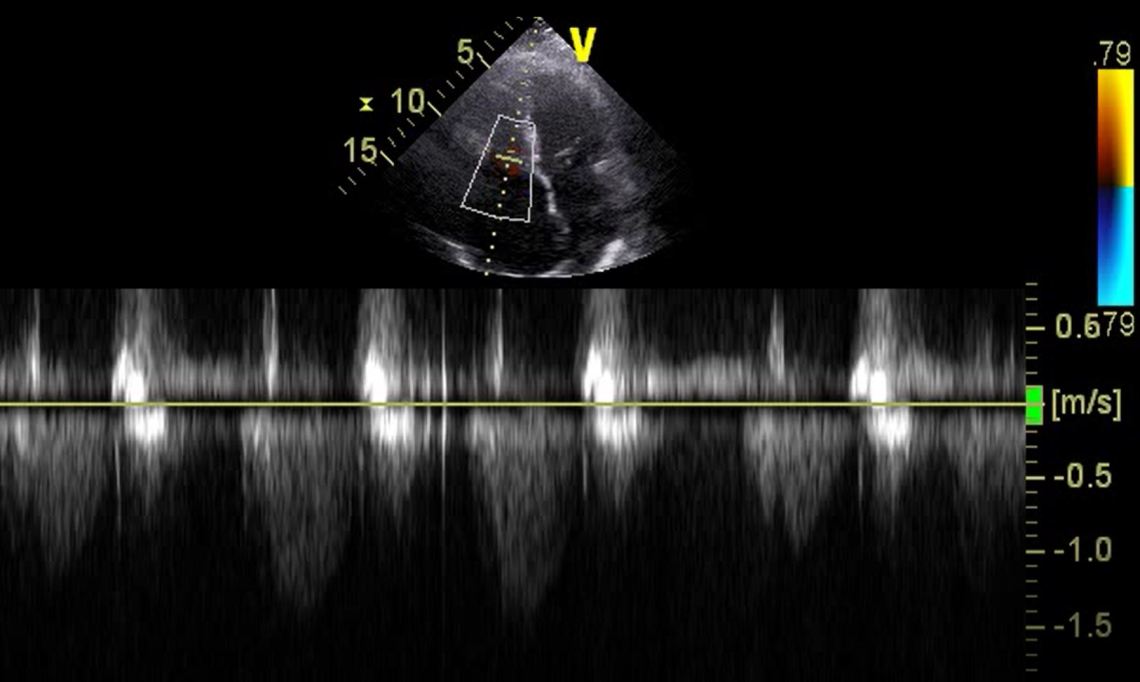

Doing what anyone would do – a TR Max Velocity. It’s >3 in PHTN. However, due to the patient’s body habitus, the image was suboptimal, and it’s difficult to determine where the true TR Jet envelope really lies on CWD. You could seriously underestimate TR VMax when the CWD is not placed in the TR Jet. It’s very unlikely this patient’s TRVMax is less than 1.5 as suggested by the image above. This is why cardiac sonographers will always try to corroborate findings on two views.

POCUS can be very misleading if images are off plane! (TRVMax here was <2, which is almost certainly an underestimate)